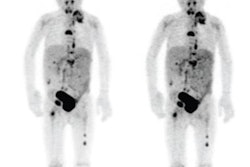

DENVER - By providing basic educational materials on nuclear medicine and the potential risks from radiation exposure, clinicians can make patients feel more comfortable about their upcoming scans, according to a presentation on Tuesday at the Society of Nuclear Medicine and Molecular Imaging (SNMMI) meeting.

By giving patients information about nuclear medicine and how safe the scans are, clinicians at Walter Reed National Military Medical Center in Bethesda, MD, found through a follow-up survey that patients better understood the specialty and had fewer concerns about their procedures.